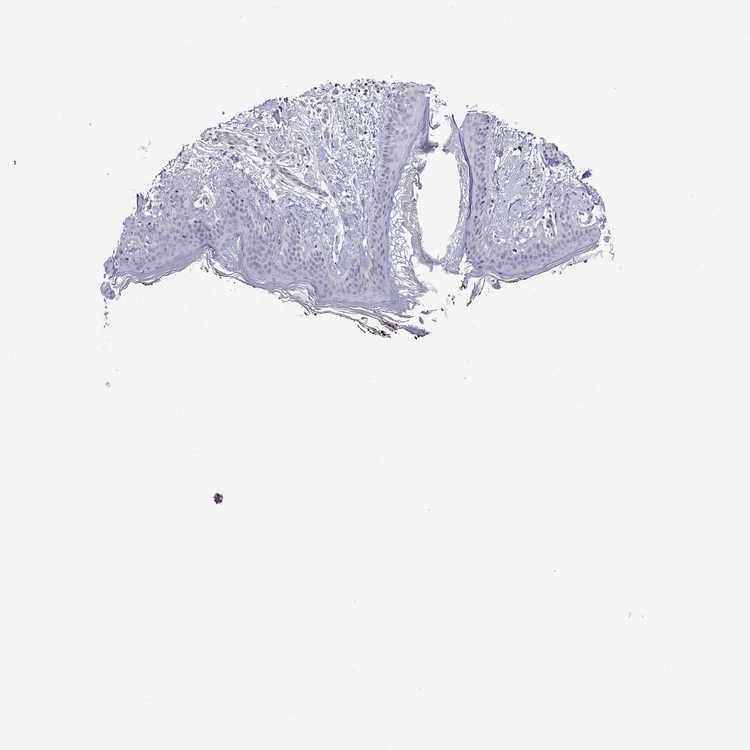

SKIN 1 - Antibody stainingi

Antibody staining in the annotated cell types in the current human tissue is reported as not detected, low, medium, or high, based on conventional immunohistochemistry profiling in selected tissues. This score is based on the combination of the staining intensity and fraction of stained cells.

Each image is clickable and will lead to virtual microscopy that enables deeper exploration of all samples and also displays staining intensity scores, fraction scores and subcellular localization as well as patient and tissue information for each sample.

Antibody HPA001242

Langerhans Not detected

Fibroblasts Not detected

Keratinocytes Not detected

Melanocytes Not detected